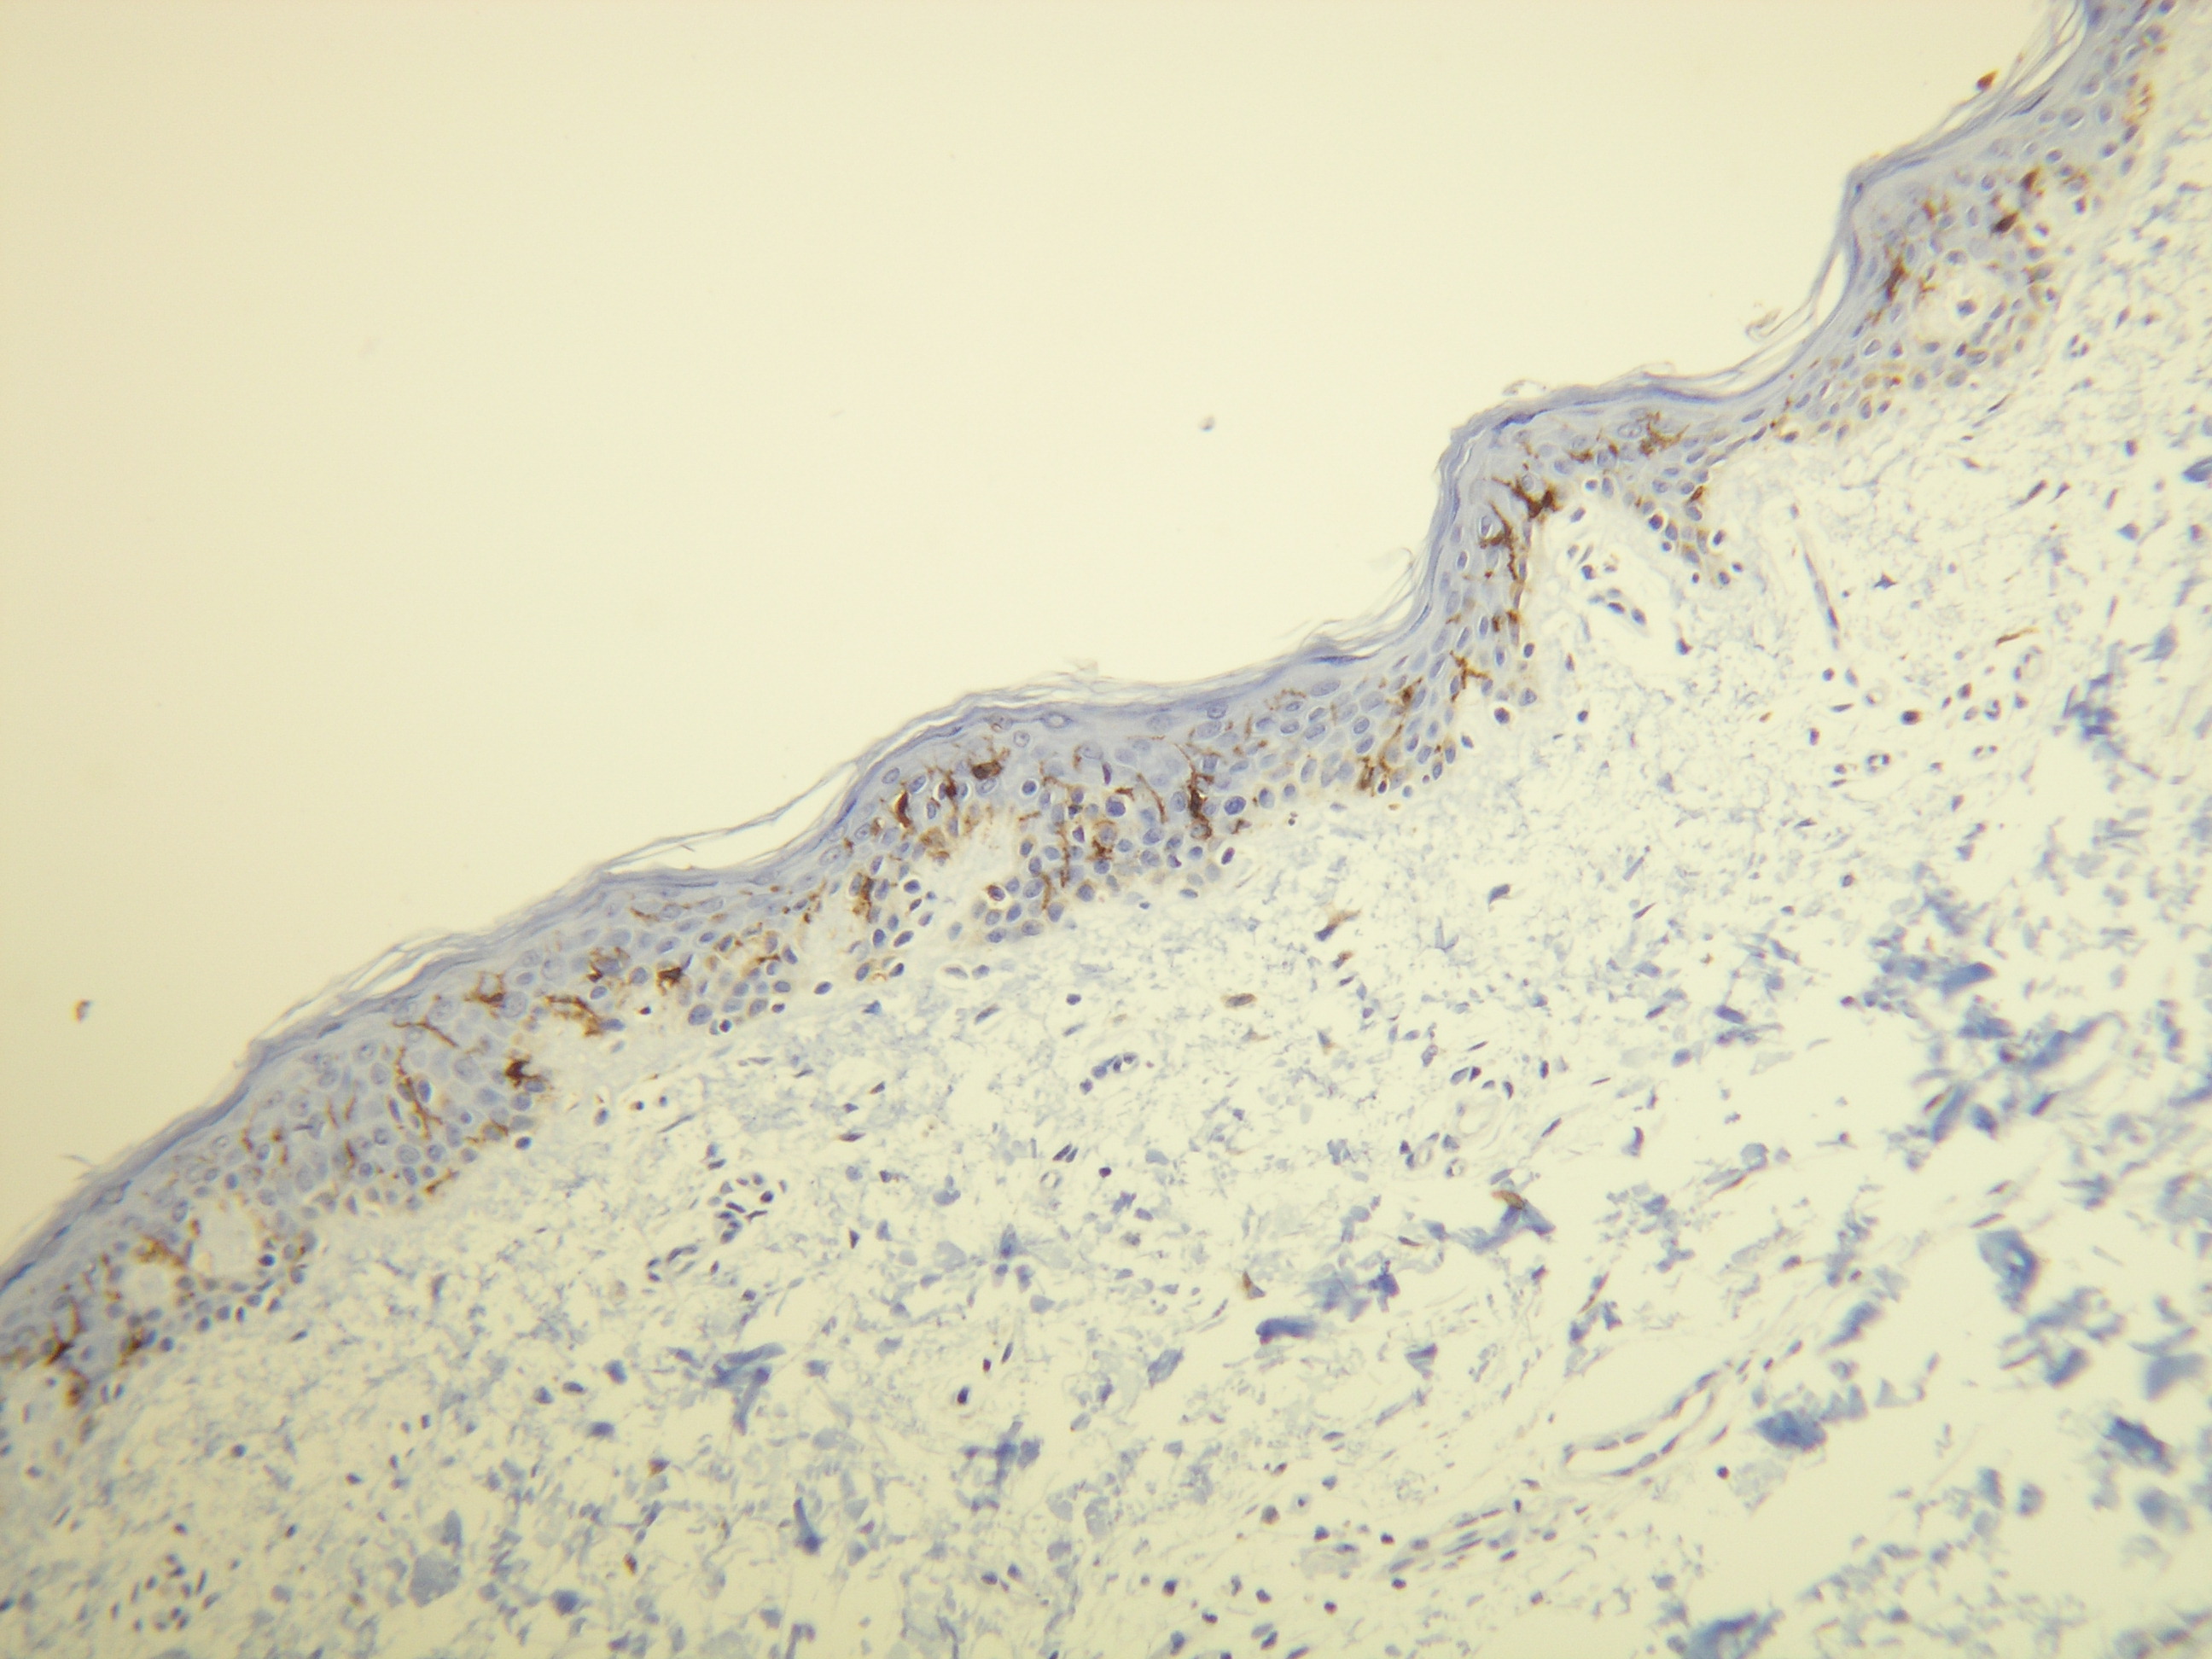

Anti-CD1a

Králičia klonálna protilátka

Peptid derivovaný z C-konca ľudského CD1a proteínu blízko transmembránovej domény. Protilátka rozpoznáva epitop umiestnený medzi Gly240 - Ala256.

IHC-P, riedenie 1:100

db071 db071-b